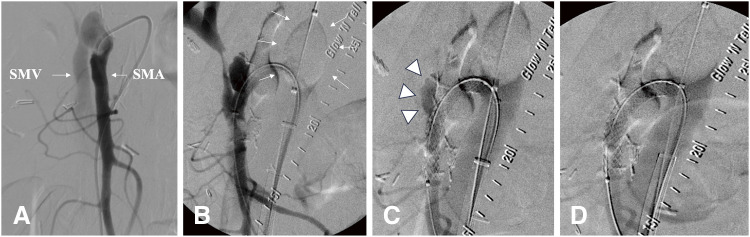

A superior mesenteric arteriovenous fistula (SMAVF) following gastrointestinal surgery represents a rare vascular complication. Enhanced computed tomography with 3-dimensional reconstruction proves to be the most efficacious modality for detecting this uncommon entity. Superior mesenteric angiography becomes imperative to accurately delineate the location and extent of mesenteric vessel involvement, which is essential for devising an optimal treatment strategy. Recently, endovascular therapy has garnered significant favor due to its less invasiveness compared to surgical interventions. Herein, we present a case of SMAVF after pancreaticoduodenectomy, manifesting with symptoms indicative of portal hypertension. Successful endovascular fistula closure using a balloon-expandable stent graft was achieved.